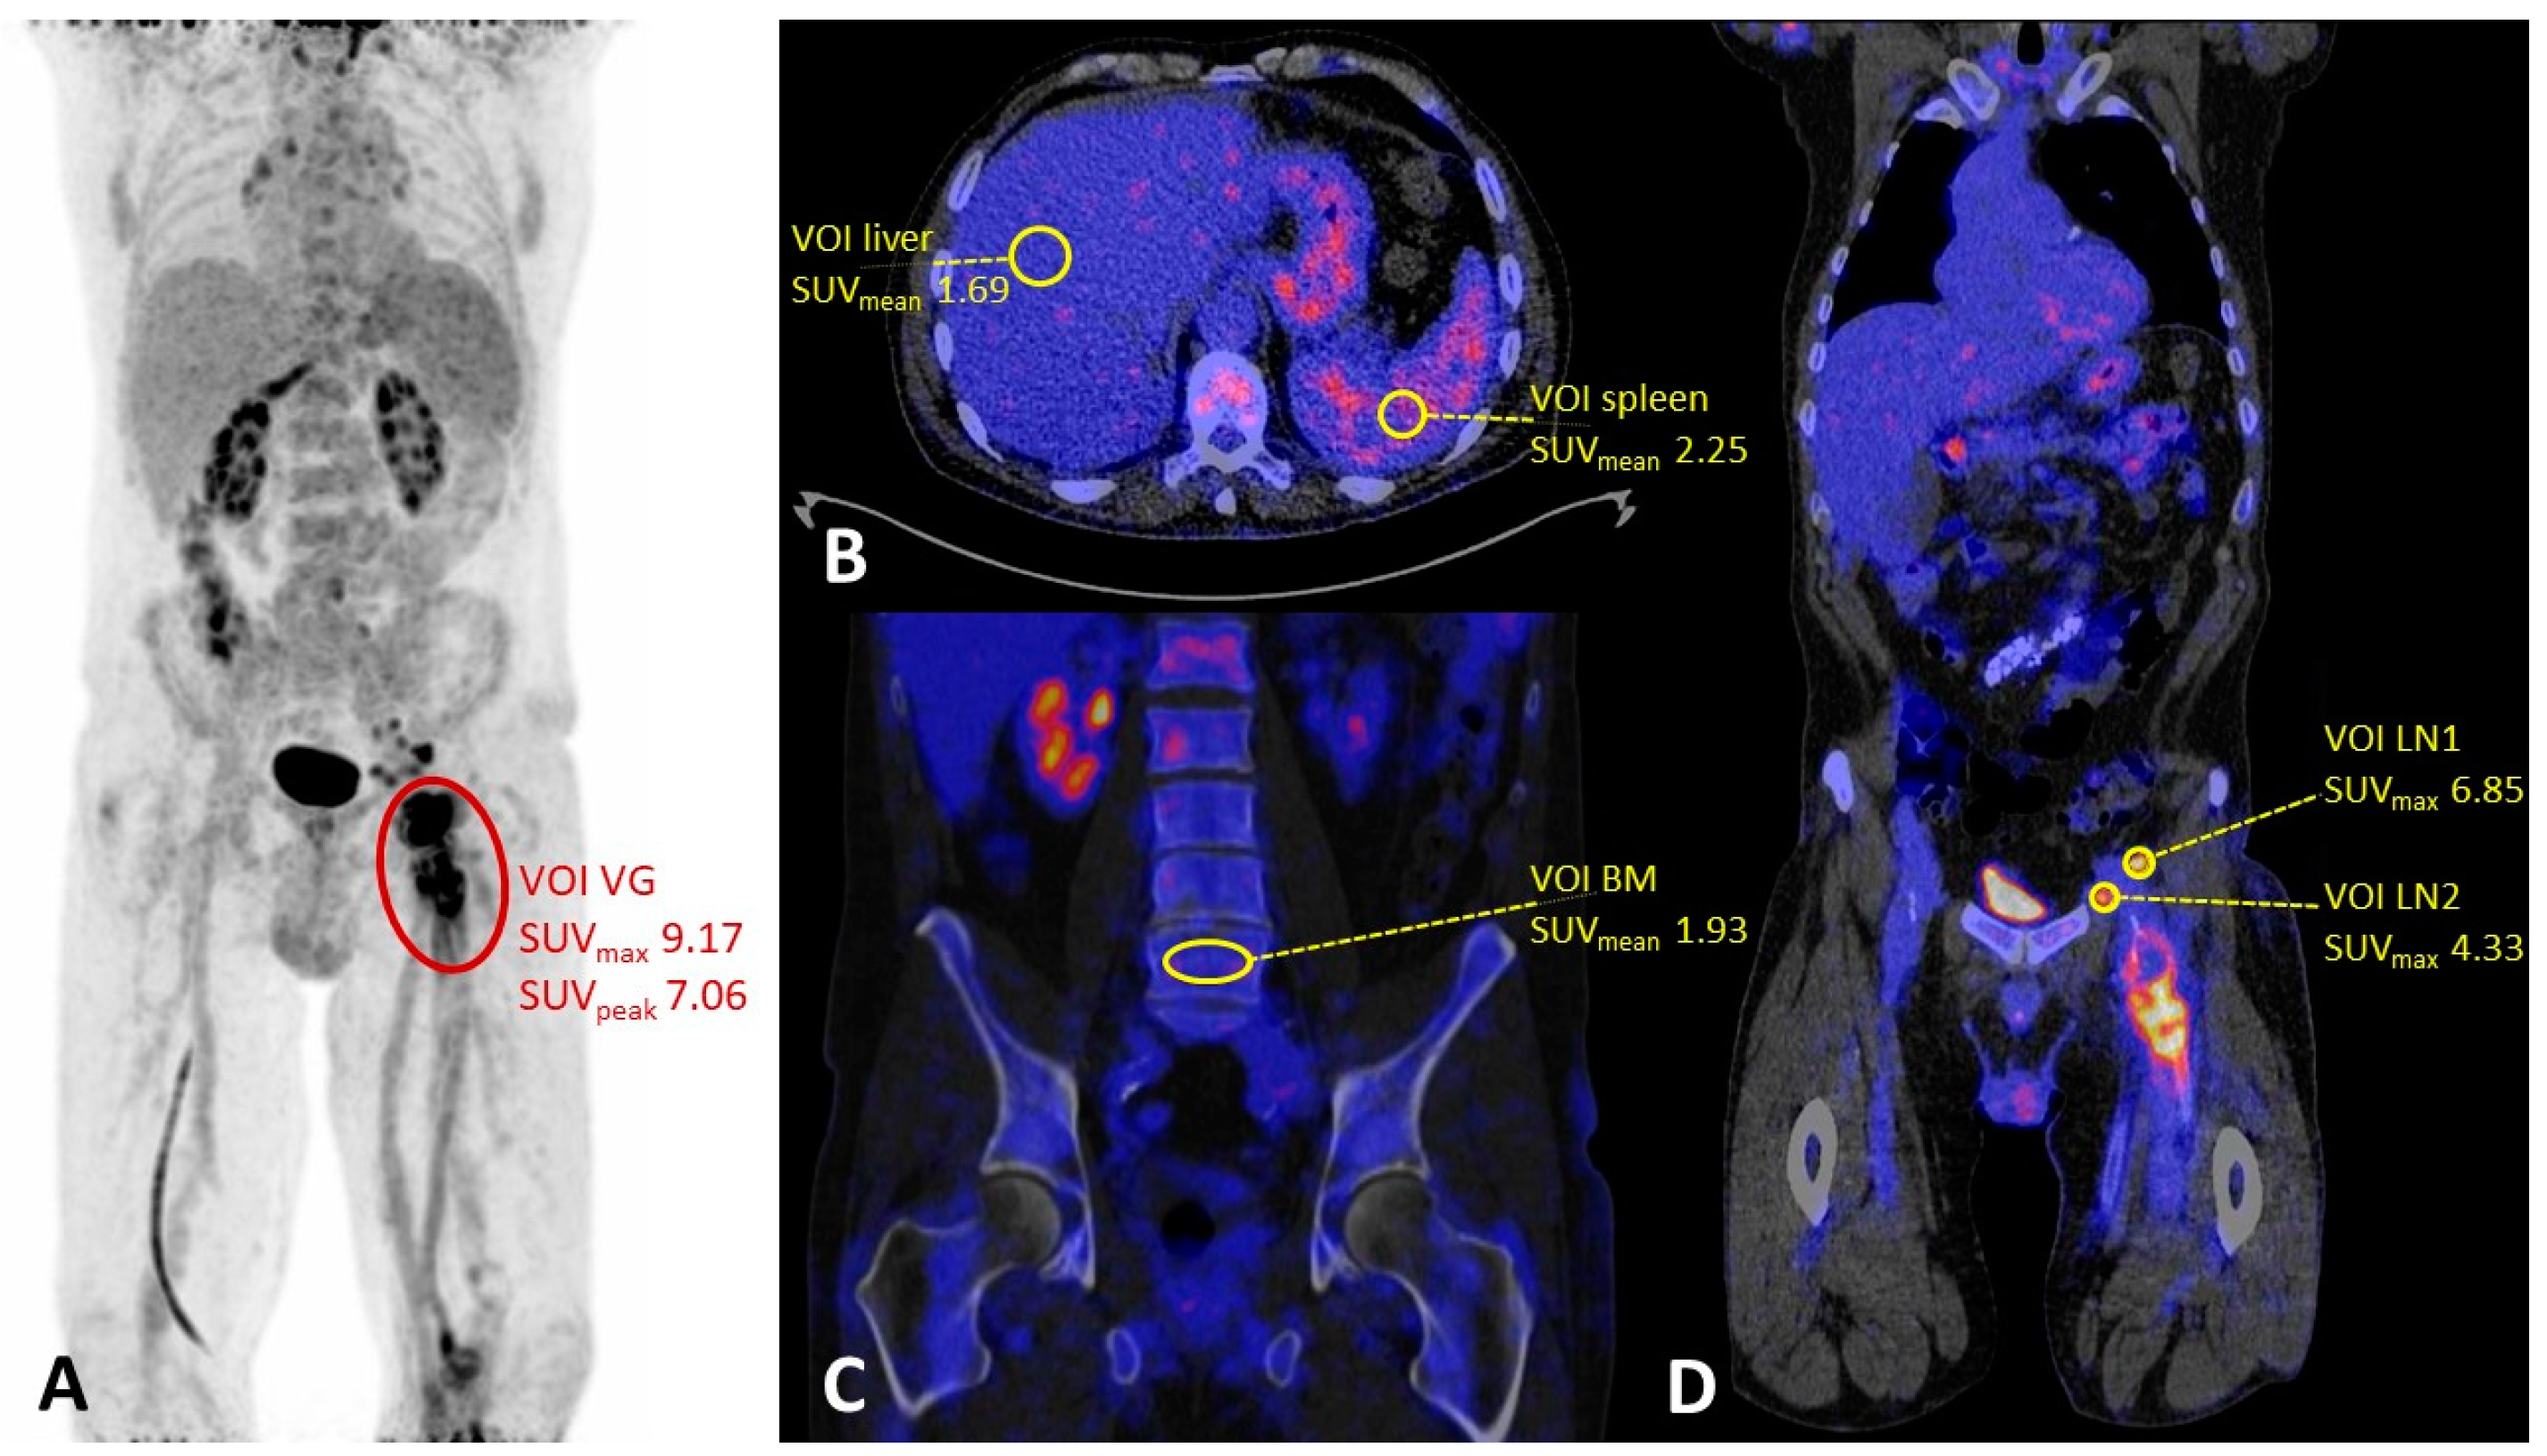

| Vascular graft—mean (SD) | ||||

| SUVmax | 9.48 (4.03) | 5.37 (2.50) | <0.001 | |

| SUVpeak | 7.27 (3.24) | 4.37 (2.05) | <0.001 | |

| Lymph nodes (n = 20)—mean (SD) | ||||

| SUVmax | 4.16 (1.61) | 2.46 * | 0.321 | |

| SUVmean—mean (SD) | ||||

| Liver | 2.50 (0.64) | 2.73 (1.01) | 0.318 | |

| Spleen | 2.47 (0.58) | 2.40 (0.84) | 0.710 | |

| Bone marrow | 2.51 (0.90) | 2.11 (0.81) | 0.062 | |